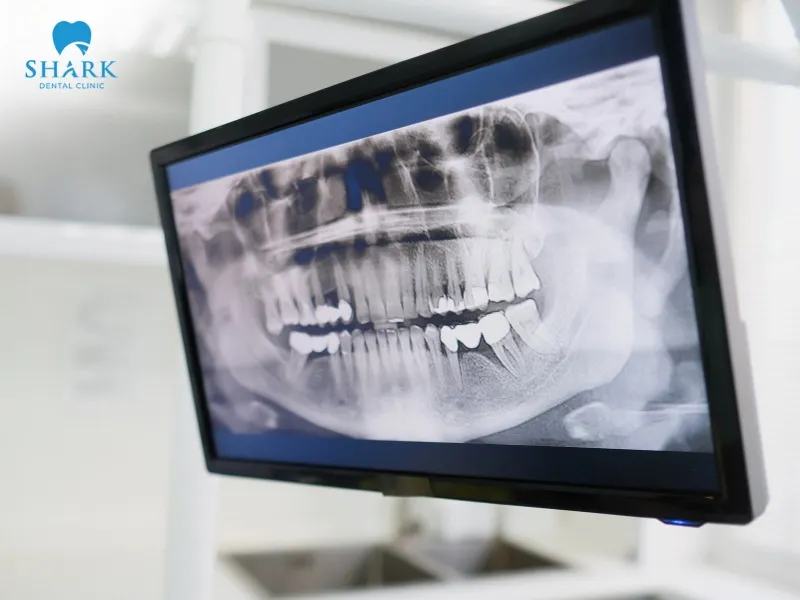

When a tooth is healthy, a dentist will see evenly colored margins on the X-ray film with moderate radiodensity. However, if an infection or dental abscess is present, the X-ray images of an abscessed tooth with an infected root canal will show several noticeable changes:

- When a tooth develops an abscess, the bone around the root tip becomes damaged. On the X-ray, this appears as a darker area compared to the surrounding healthy bone. This dark region may be oval or round, and the larger the dark patch, the more severe the abscess is. Dentists rely on this contrast when learning how to read a dental X-ray accurately.

- In healthy tooth structures, a thin line surrounds the root tip. However, when there is an infection or abscess, these margins become thicker or may appear faded. This is a warning sign that the area around the root tip is being destroyed by inflammation.

- In some cases, the dark area around the root tip appears perfectly round with a clear border, indicating that the abscess has existed for a long time. If the dark area spreads widely with an unclear margin, it may indicate a progressing infection with ongoing bone resorption.

- If the tooth has not undergone root canal treatment and the canal remains healthy, the X-ray will clearly show the root canal running from the crown down to the root tip. Conversely, if an infection is present, the canal may appear narrow or calcified, which can be observed on the X-ray film.